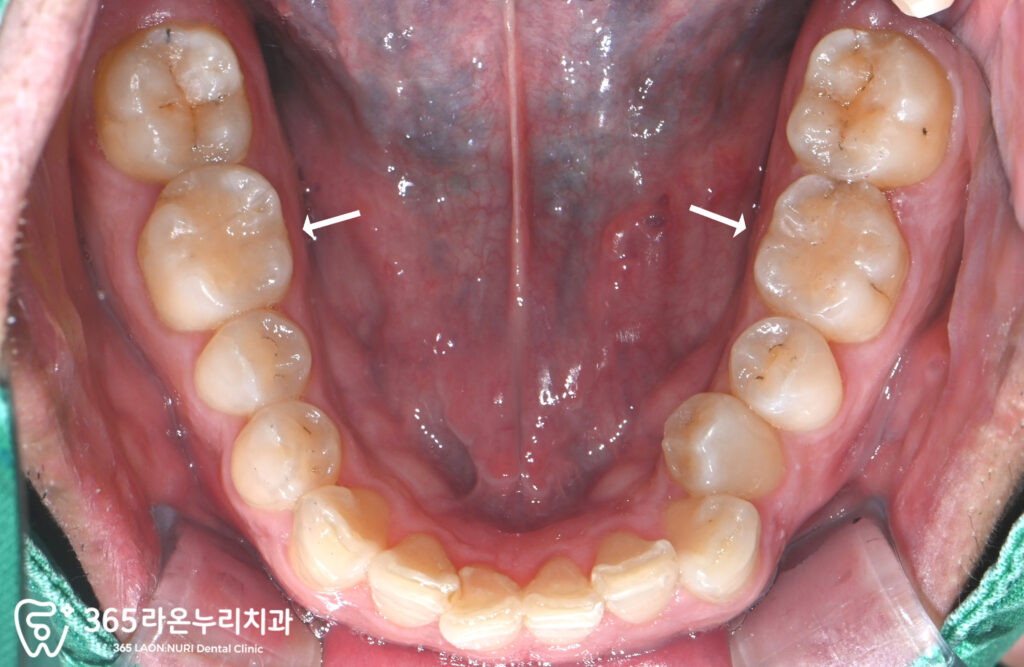

치료 후 구강 내 사진

신장동 치과 에서 치료가 완료된 곳에

표시를 해봤습니다.

이 표시가 없었다면

치료를 했는지 모를만큼

자연스러운 모습을 볼 수 있습니다.

하악의 어금니도 레진으로 수복함으로써

모든 치료가 마무리 되었습니다.